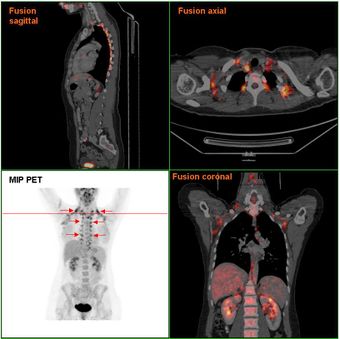

النسيج الشحمي الأسمر لدى إمرأة تجري فحص PET/CT exam